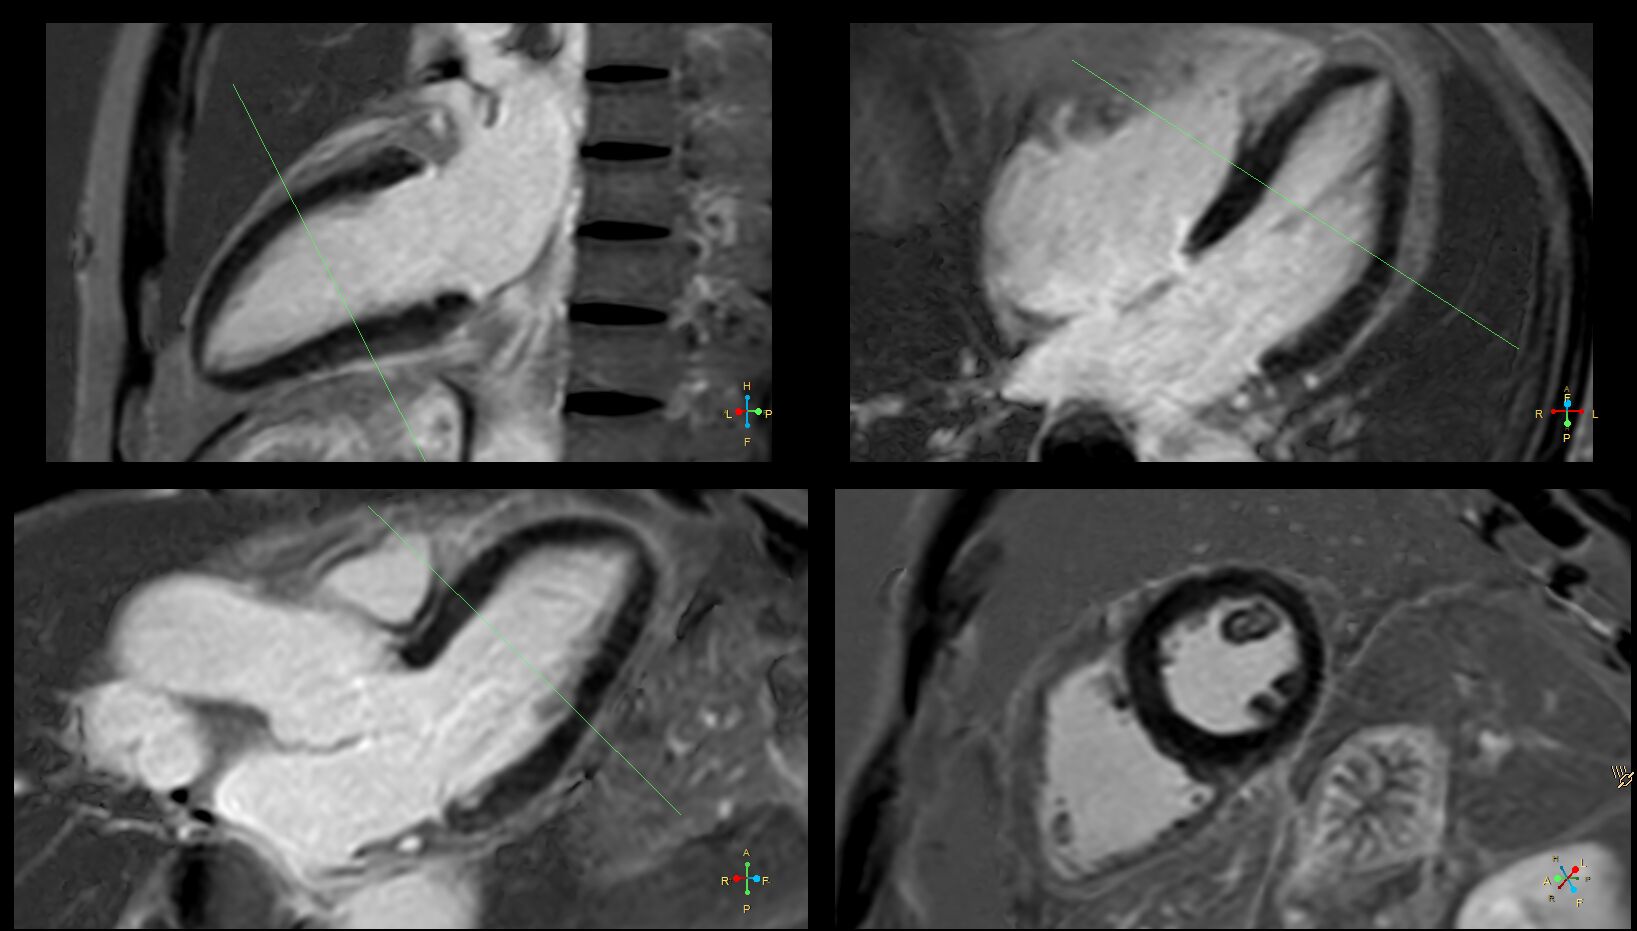

(Structure , Viability) 注射完顯影劑後的Early Gad(看有沒thrombus) 和 Late Gad 額外還有Tagging .

也可以在注射完顯影劑後在有限時間內作Late Gad的造影。

(用Time Locer 找TI . 要有ECG , 要忍氣或用Respiration trigger.)

Late Gad 提供Viability 資訊, 不是Functional.